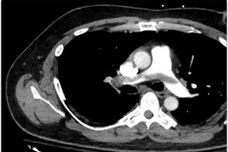

The Pulmonary Embolism Response Team (PERT) is made up of specialists from Critical Care Medicine, Interventional Radiology, and Thrombosis. The purpose is to provide physicians and their patients rapid access to a multidisciplinary team of experts in dealing with life-threatening pulmonary emboli